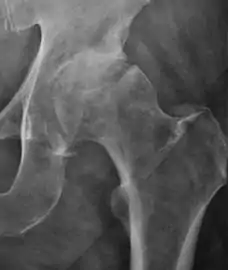

- Slipped capital femoral epiphyses (SCFE)

Slipped capital femoral epiphyses (SCFE) usually affect 11- to 14-year-old adolescents (Figure 4). Radiographs may show widening and irregularity of the physis and posterior inferior displacement of the capital femoral epiphysis. On the AP view Klein’s line, tangent to the lateral aspect of the femoral neck, does not intersect the femoral head indicating that it is displaced. SCFE may compromise the blood supply to the femoral head and cause avascular necrosis, mainly when there is instability between the fragments.[1]

Figure 4: (a) X-ray of a 10-year-old child with left hip pain. It was considered normal at emergency despite the widening of the left physis (arrow). Two weeks later epiphysiolysis was evident (b). Despite appropriate surgical reduction (c) osteonecrosis developed and femoral head collapsed 1 month later (d).[1]